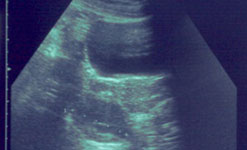

|  |  | An ultrasound scan showing PCOS cysts on an ovary |

Polycystic Ovary Syndrome

In this week’s Check Up, Barbara Myers and her guest Professor Adam Balen from Leeds General Infirmary will be offering advice about Polycystic Ovary Syndrome.

Weight gain, excessive body hair, acne and irregular periods are just some of a myriad of symptoms that women with polycystic ovary syndrome (PCOS) can suffer from.